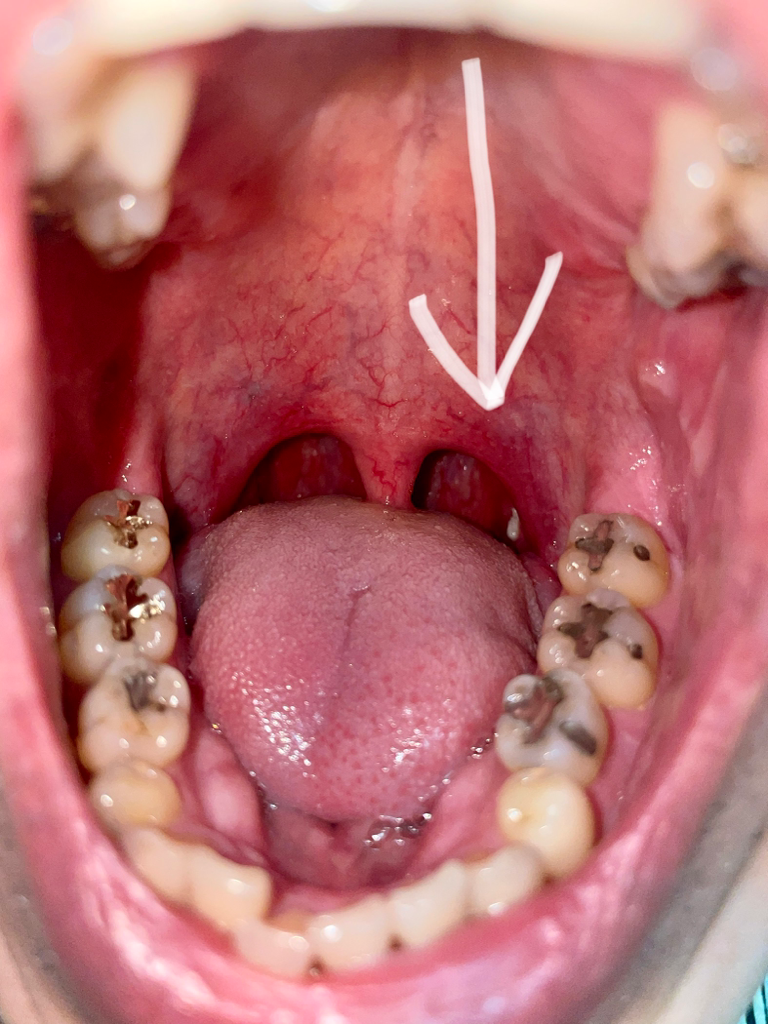

사진상에 보시면 목젖 뒤에 오른똑 자그맣게 하얀 부분 보이시나요?? 이런적은 처음인데 왜 저러런건가요??일주일은 안댓고 한3-4일 된거 같아요

• 1번 째 사진